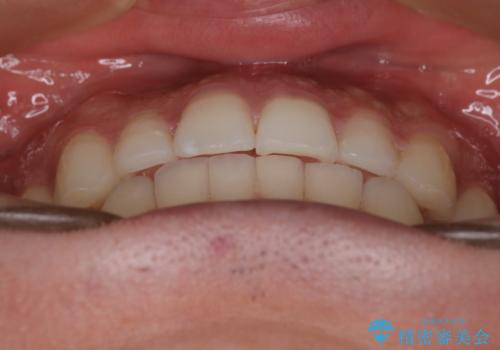

- 前歯の歯並びの改善を希望され来院された患者様です。

初診時の歯並びの状態としては、上下ともに前歯部の中等度以上のがたつき(叢生)があり、右の前歯が1本飛び出した状態でした。

抜歯は行わず上下顎ともに、主に歯列弓の拡大とディスキング(歯と歯の間に隙間を作る処置)を行い叢生を改善しました。

矯正装置としてはマウスピースを使用しています。

見た目、嚙み合わせ及び、治療期間や施術内容に大変ご満足いただきました。